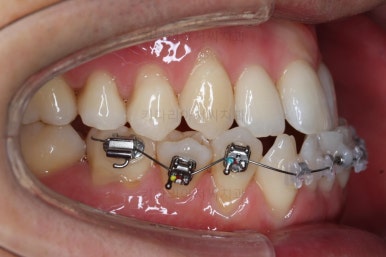

장치를 처음 부착했을 때의 입안 모습입니다.

아랫니가 해야될 작업이 많고 기간이 오래 걸리기 때문에 윗니는 최대한 늦게 장치를 부착하여 불편감을 최소화 하기로 했어요.

이번에 사용한 장치는 자가결찰 세라믹장치입니다. Empower clear(엠파워 클리어)라는 장치이고 흔히 많이들 알고계신 클리피씨와 동일한 유형의 장치에요.

이 뽑은 자리로 앞니를 쭈욱 밀어넣으며 비대칭도 맞춰주기 위해서 미니스크류(마이크로 임플란트)라고 불리는 작은 나사를 잇몸뼈에 식립했어요.

이를 지지대로 삼아서 치아를 움직이게 됩니다.

아랫니를 계속 당겨주면서 가지런하게 하고 있어요.